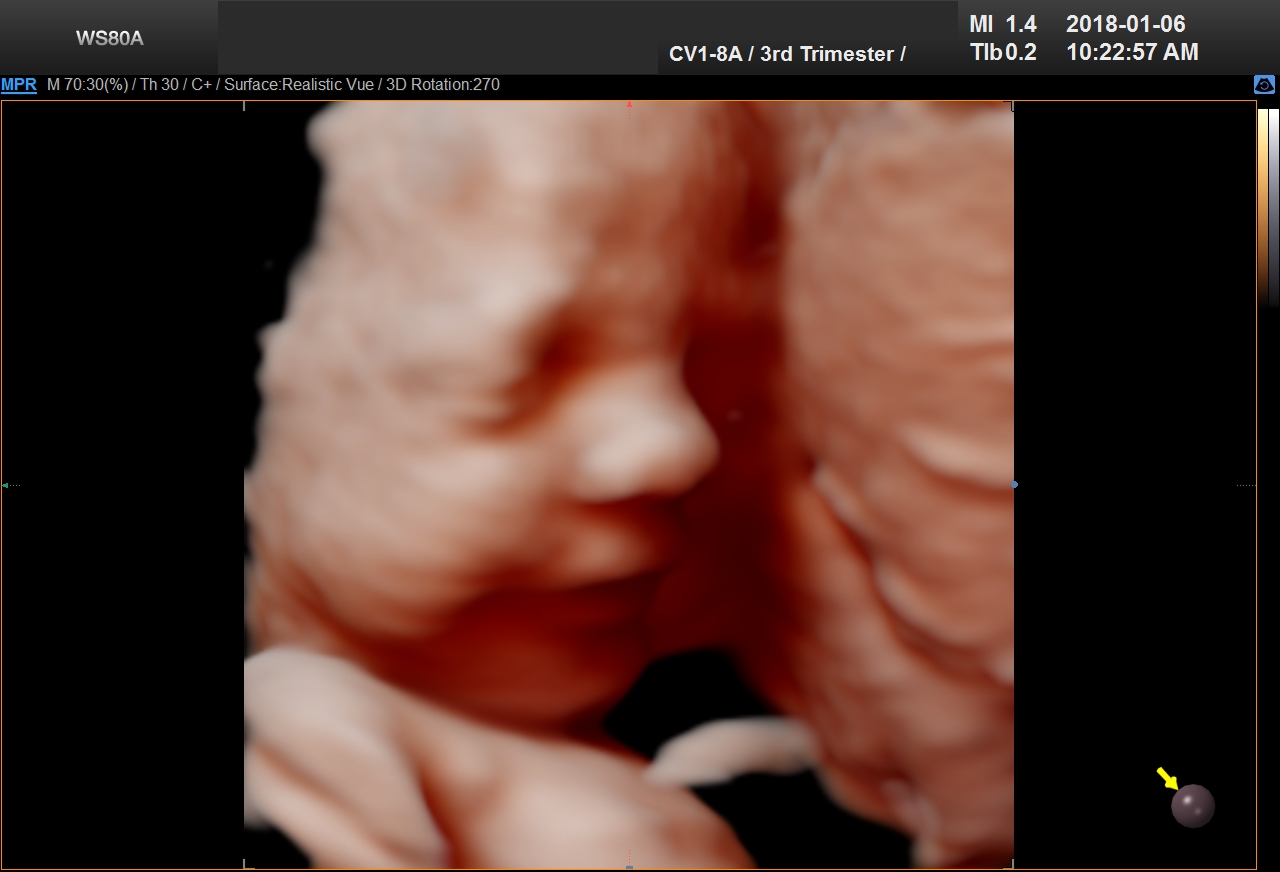

5D Ultrasound

5D Ultrasound is the newest development in pregnancy imaging and it is patented by Samsung. It captures and combines high definition volume data to create automated images with amazing color and clarity. The bond between a new baby and the family gets even stronger when the family can view realistic pictures of baby in a 5D ultrasound.

UC Baby’s Latest 5D Ultrasound Service Offering

UC Baby Calgary is the first facility which brought cutting edge 5D technology to Canada. This cutting edge new ultrasound machine provides realistic pictures of the baby using the most advanced features of ultrasound imaging. We are offering high-definition 5D ultrasound technology to create unforgettable memories without extra cost. This new ultrasound technology allows families to bond stronger to the baby, with clear views of baby’s face and movements. With 5D technology, it is even possible to notice the dimples when baby smiles!

The best time to have a 5D ultrasound is between 24-32 weeks of pregnancy. Our experienced and professionally trained staff are there to amaze the mothers and their families. We also offer free online accounts for captured 2D, 3D, 4D and 5D images / videos in addition to free live broadcast of the whole ultrasound session. This is the fastest and easiest way to share baby’s first pictures and videos with friends and family instantly.